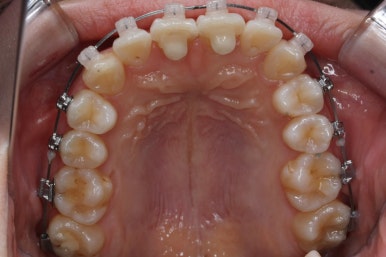

위 사진은 연산동교정치과 처음 내원하셨을 때의 입안 모습입니다. 몇 가지 모습이 관찰됩니다.

치아가 삐뚤삐뚤합니다.

위~아래 앞니가 많이 겹쳐서 아랫니가 많이 모이지 않는 "과개교합" 입니다.

앞니가 앞으로 뻐뜨러져 있습니다.